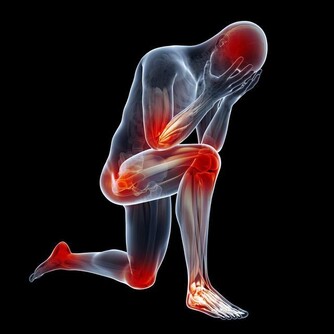

糖尿病患者體內的血糖過高,糖分是細菌的充足營養,所以糖尿病患者如果出現了皮膚上的傷口,細菌就很容易進入到傷口處並且大量的繁殖,這樣就會導致傷口由很小的面積潰破到很大的面積,這樣癒合起來就很難了。

常常有看到這樣的患者,患者本身糖尿病,血糖控制不好,導致受壓迫的部位常常潰破,有的時候,腐肉去不了,新肉也生不上來,長時間的遷延不愈,最嚴重的患者最後會有小的傷口潰破直接導致潰爛至骨頭。